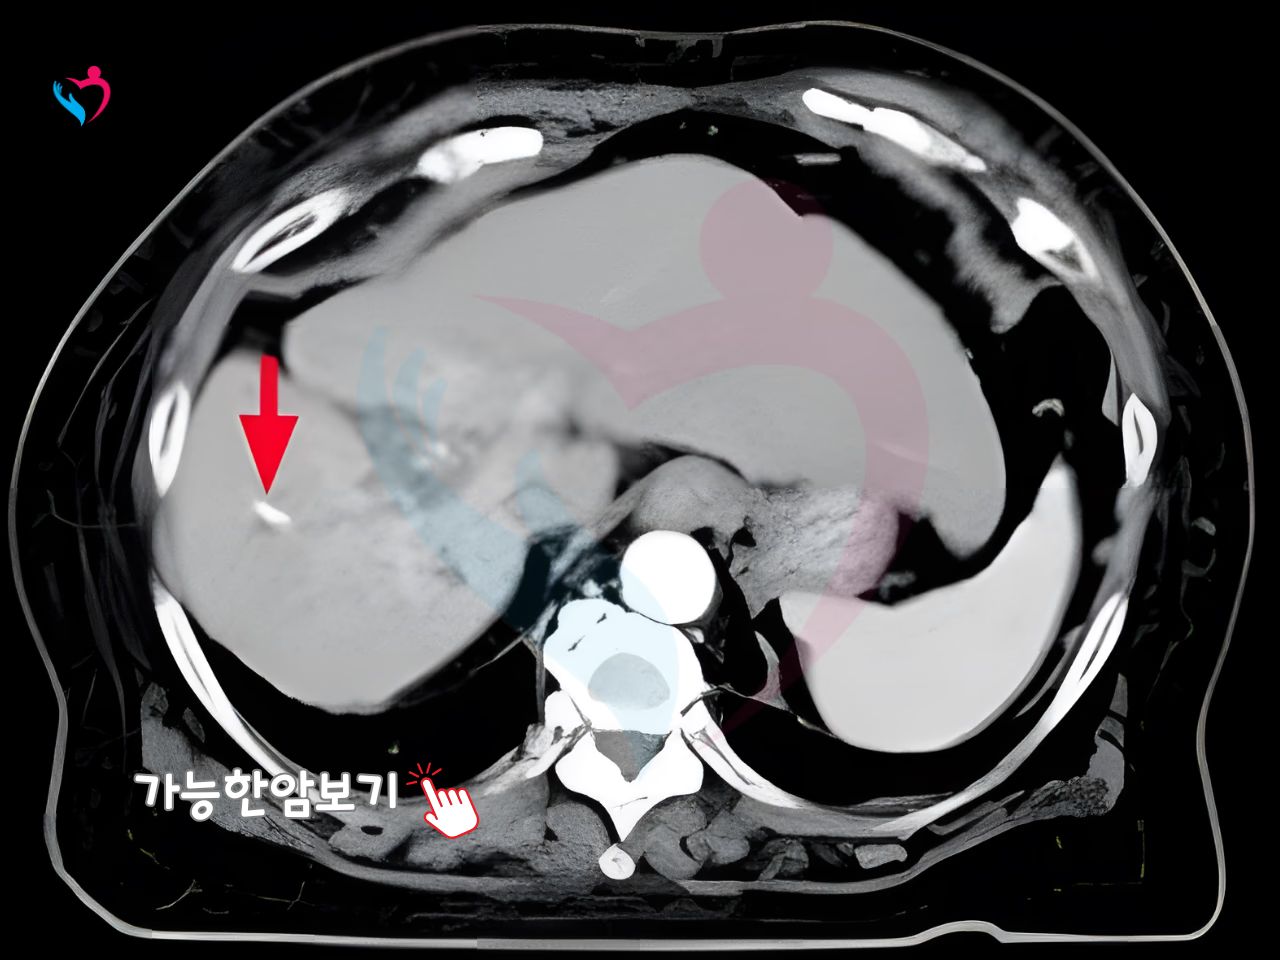

전이 재발로 수술이 힘든암 가능성 확인

수술 불가한 전이 재발암, 일본중입자치료로 길을 찾으세요. 중입자암치료 가능 여부를 1~2일 내 확인해 중입자치료비용 등 맞춤 대안을 안내 합니다.

중입자치료가 어렵다고 판단되셨나요? 전이 재발이 있어도 확인이 필요합니다. 암의위치에따라 선택지가 달라집니다. 재발암도 상황에따라 달라집니다.

수술 없이 1.2mm 미세 바늘로 종양을 제거하는 고주파 소작술은 흉터가 거의 없고 다음날 즉시 치료 확인이 가능합니다. 간, 폐, 유방의 전이암까지 정밀 타격해 일상 복귀를 앞당깁니다.